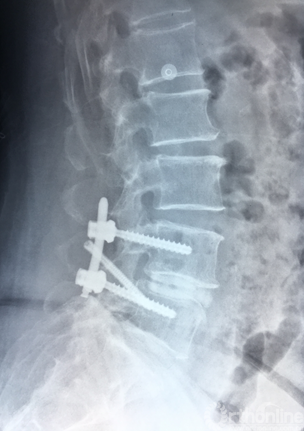

术后正、侧位片

术后三维SCT确认融合器,钉棒植入位置满意

MRI失状位融合器、植骨位置及滑脱复位情况